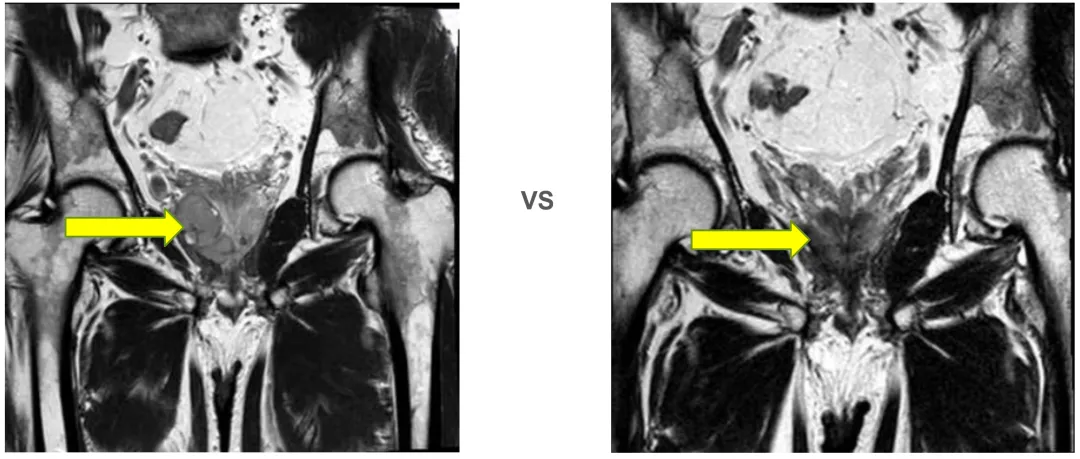

前列腺MRI(2024-11-28)

前列腺右侧周围带可疑肿瘤,与右侧肛提肌分界欠清、前列腺增生伴钙化、右侧股骨头异常信号灶,考虑退行性改变。

前列腺大小约为4.9cm×4.9cm×3.5cm,形态异常,右侧包膜欠光整,右侧周围带见团块状异常信号灶,T2WI等低信号,T1WI低信号,DWI明显增高,边界欠清,长径约为3.9cm,与右侧肛提肌分界不清,略受推挤向外侧移位。

左侧周围带信号不均匀减低,中央带及移行带信号不均,其内见斑片状极低信号影。双侧精囊腺对称,充盈欠佳。膀胱充盈欠佳,其内未见异常信号灶。直肠周围脂肪间隙未见异常。扫描野内未见明显肿大淋巴结。扫描野内右侧股骨头内见斑片状异常信号灶。

1. 考虑前列腺右侧周围带肿瘤,与右侧肛提肌分界欠清。

2. 前列腺增生,伴钙化。

3. 右侧股骨头异常信号灶,考虑退行性改变。

2025年9月12日 前列腺平扫+弥散(DWI)

(2024-11-28 vs 2025-9-12)

前列腺大小约为3.4cmx3.3cmx3.0cm,形态异常,右侧包膜欠光整,右侧周围带见结节状异常信号灶,T2WI低信号,T1WI低信号,DWI信号不高,边界欠清,长径约为0.9cm,左侧周围带信号不均匀减低,中央带及移行带信号不均。双侧精囊腺对称,充盈尚可。膀胱充盈可,其内未见异常信号灶。直肠因围脂肪间隙未见异常。扫描野内未见明显肿大淋巴结,扫描野内右侧股骨头及髋臼内见斑片状异常信号灶。

1. 结合病史,考虑前列腺右侧周围带肿瘤治疗后改变。

2. 右侧股骨头及髋臼异常信号灶,考虑退行性变可能。

前述改变与前片(2025-06)比较未见明显变化,建议隔期复查。